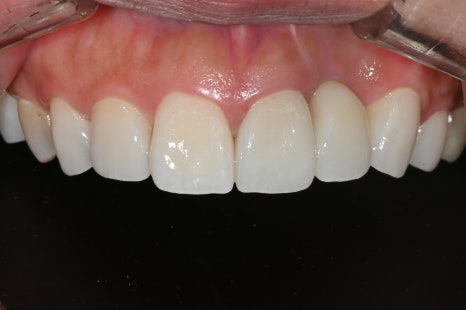

왼쪽 사진: 치료 후 정면 모습입니다. 옆 치아와 조화롭게 어우러져, 환하게 웃을 수 있는 앞니 라인이 완성되었습니다.